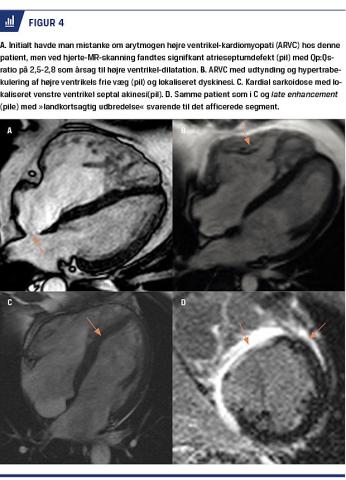

Pludselig død før 50-årsalderen skyldes i knap 10% af tilfældene ARVC, og mindst en tredjedel forekommer familiært. Afficerede områder dilaterer, særligt i højre ventrikel, og myokardiet erstattes delvist af fibrose og fedt. ARVC er en syndromdiagnose, hvor en kombination af en række forskellige kriterier (minore og majore) kan udløse diagnosen [25]. CMR er ikke nødvendig for at stille diagnosen, men information fra CMR søges ofte, da CMR er særligt velegnet til visualisering af højre ventrikel og vurdering af højre ventrikels kontraktionsmønster. CMR vil vise akinesi, dyskinesi eller dyssynkroni i højre ventrikels frie, tynde væg og af og til fibrose samt evt. mikroaneurismer (Figur 4A, B). Fund af fænotype, som er forenelig med ARVC og samtidig dilatation af højre ventrikel (> 90 ml/m2 for kvinder og > 100 ml/m2 for mænd) betragtes som foreneligt med ARVC. Med CMR forsøger man samtidig at udelukke andre årsager til højre ventrikel-dilatation

f.eks. atrieseptumdefekt med venstre-højre-shunt

(Figur 4A).

Ved kardial sarkoidose er granulomer årsag til isolerede »udflydende« områder med late enhancement uden særligt prædilektionssted (Figur 4, Figur 2C, D). Biopsi er guldstandard, men late enhancement-undersøgelse vil, særligt hos patienter, som har fået konstateret anden verificeret sarkoidose, ofte give et karakteristisk resultat. Patienter, hos hvem der initialt er mistanke om kardial sarkoidose, og hos hvem der ikke ved

CMR kan påvises granulomer, har lav risiko for kom-plikationer, mens påviselig late enhancement øger

den årlige risiko for pludselig død tyve fold [18],

hvorfor man ofte vælger ICD-implantation hos disse

patienter.